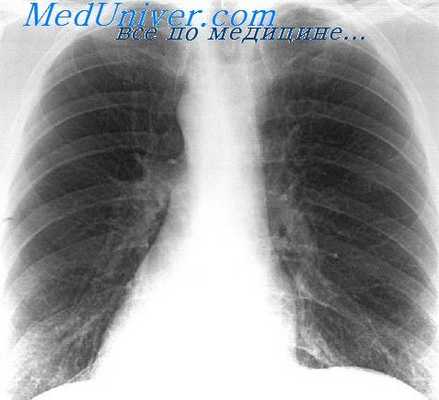

Рентгенологический метод традиционно применяется для оценки функции внешнего дыхания. В пульмонологической клинике перед рентгено-функциональными методами ставятся две задачи: 1) наряду с рентгено-морфологическими признаками помочь рентгенологу в постановке рентгенологического диагноза; 2) предоставить дополнительную информацию о легочных объемах, вентиляции и кровотоке, получение которой методами функциональной диагностики невозможно или слишком обременительно. Естественно, что в данной главе рассматривается только вторая сторона рентгено-функциональных методов.

Для изучения легочной вентиляции предложен ряд специальных рентгенологических методов, к которым относятся рентгенокимография, полиграфия (диплография), рентгенопневмография, денсография и др.

Дыхательная рентгенокимография — один из старейших рентгено-функциональных методов, предложенный еще в 1911 году польским врачом Sabat. Рентгенокимография обеспечивает объективную регистрацию состояния движения органа во времени и дает возможность сравнивать участие далеко расположенных его отделов или различных органов (К. В. Помельцов, 1965).

Принцип рентгенокимографии заключается в том, что контуры движущихся органов на снимке имеют форму зубчатой кривой, причем высота зубца отражает величину, а ширина у основания — время смещения. Технически это осуществляется путем прохождения рентгеновых лучей через узкую щель (0,5 мм) в свинцовой пластинке или решетку, в которой щели расположены на расстоянии 12 мм друг от друга (многощелевой кимограф). Во время производства снимка решетка или кассета с пленкой приводится в движение, причем больной продолжает дышать.

В настоящее время наиболее распространена многощелевая непрерывная рентгенокимография, при которой движется решетка, а кассета с пленкой остается неподвижной. При дыхательной рентгенокимографии щели решетки обычно располагают вертикально, так как в этом направлении происходит основной компонент движения диафрагмы и ребер. Исследование производят в двух проекциях — передней (прямой) и боковой, причем переднюю рентгенокимограмму обычно производят при спокойном дыхании, а боковую — при глубоком (Л. Д. Линденбратен, 1960).

Анализ дыхательной рентгенокимограммы заключается в изучении формы дыхательных зубцов и сравнении зубцов диафрагмы и ребер. Каждый дыхательный зубец состоит из двух колен: крутого и более короткого колена вдоха и пологого удлиненного колена выдоха. Удлинение колена выдоха служит признаком обструктивной дыхательной недостаточности.

Сравнительное изучение зубцов различных участков диафрагмы и ребер может указать на неравномерность вентиляции различных отделов легкого, но чаще всего деформация зубцов отмечается при плевро-диафрагмальных и плевро-костальных сращениях.

Я. Л. Шик (1936) предложил измерять диафрагмально-реберный коэффициент, который позволяет объективно анализировать и характеризовать типы дыхания. Диафрагмально-реберный коэффициент (сокращенное обозначение — ДРК) представляет отношение амплитуды зубцов диафрагмы к амплитуде зубцов заднего отдела V ребра. Грудному типу дыхания соответствует ДРК не более 3, брюшному — 6 и выше. ДРК от 3 до 6 относится к смешанному типу дыхания.

Е. Л. Кевеш и В. И. Бураковский (1955) провели сравнительное изучение рентгенокимографии у легочных больных. Они считают, что дыхательная рентгенокимография представляет ценный метод, дающий возможность получить сравнительное представление о вентиляционной способности одного легкого по отношению к другому. Однако возможности его ограничены, так как не позволяют установить поглощение кислорода, определяющее эффективность дыхания. Поэтому, по мнению Е. Л. Кевеша и В. И. Бураковского, рентгенокимография, спирография и бронхоспирометрия должны дополнять друг друга и служить для комплексного углубленного изучения дыхательной функции легких в клинике грудной хирургии.